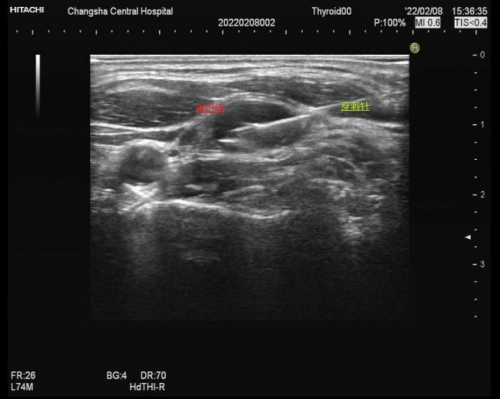

来自长沙市岳麓区的李女士过年前洗脸时摸到脖子右边有几个坨,大的有核桃大小,小的也有花生米大小,不痛不痒。李女士忙着过年置办年货、搞卫生,也没有时间多去关注。等到年后,这几个坨越长越大,脖子左侧上也有了,才着急到维多利亚老品牌76696vic来检查。耳鼻喉科医生摸了下,发现这些坨有些推不太动,首先怀疑是淋巴结的问题,于是马上开了超声检查。超声检查发现颈部双侧均可见多发的肿大淋巴结,淋巴结内结构破坏,并且部分融合在了一起,内部血流信号丰富,高度怀疑淋巴瘤,并进行穿刺活检。紧接着,李女士在超声引导下进行了淋巴结穿刺活检,后期病理切片结合免疫组化确诊为淋巴瘤,随后医生安排李女士住进了血液科,进行了一系列治疗后已经好转出院了。

还有就是一些肿瘤性病变,如淋巴结自身的病变淋巴瘤,还有头颈部肿瘤如鼻咽癌、舌癌、甲状腺癌、牙龈癌等,还有乳腺癌、肺癌、肝癌、胃癌等均可能出现颈部淋巴结肿大。各部位病变淋巴结肿大的位置稍有不同:甲状腺癌、鼻咽癌、舌癌等头颈部癌以颈部两侧为主;乳腺癌、肺癌、肝癌、胃癌以同侧锁骨上的淋巴结肿大为主;淋巴瘤则无明显规律,而这些淋巴结肿大通过超声检查一般都会发现淋巴结内部结构破坏,呈类圆形,部分结节出现融合,血流也较丰富,需要高度警惕并进一步检查。另外还有一些特殊的淋巴结病变,相对少见,如木村病、Castlman病等。

颈部的“坨”来源如此复杂,当我们摸到颈部有异常时,应该及时到医院检查。首选的就是超声检查,彩超可以明确肿块是实性还是囊性,可以观察肿块周围的器官组织、与血管的关系如何、了解肿块的大致来源,也可对肿块的内部结构进行观察,是否有结构破坏,还可观察肿块内部血流情况,进行初步的诊断。当彩超判断需要进一步检查还可以进行超声造影,最重要的是可以在超声引导下进行穿刺活检,取出少量组织进行病理切片,将组织放到显微镜下进行观察。超声引导下肿块穿刺创伤小、安全性高。病人血常规、凝血功能正常的情况下,穿刺后观察半小时就可以回家,有80%以上的肿块可以明确诊断。当然穿刺也有局限性,有些因为取材有限,后期还需要进行免疫组化检查,甚至需要手术取出整个淋巴结才能确诊。

超声引导下颈部淋巴结穿刺术